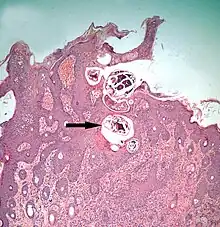

The diagram Mite infestation sites on skin shows where typical infestations of different taxonomic groups mites on livestock animals occur on or in the host's skin.[9] The position of these mites in relation to the skin or other organs is crucial for their feeding and also for their veterinary diagnosis and options for treatment. The mites either feed on the tissues of the skin using penetrating mouthparts or on the inflammatory exudate that results from the action of the mouthparts and saliva of the mites on the skin.[12] Demodectic mites have mouthparts adapted to penetrate and suck out the contents of individual cells of hair follicles.[13] It is usual for all active stages of the mite lifecycle to feed as parasites, but the trombiculid mites are an exception. Most of the parasitic mites do not feed directly on blood, but the dermanyssid mites and larval trombiculid mites directly suck up capillary blood as their exclusive food. The tube through which food is ingested and saliva excreted during feeding is formed in most mites by apposing the sheath that contains the chelicerae against the hypostome. However, the trombiculids are an exception. Some species of mites (Analgidae) have adapted to feeding on keratin and skin debris amongst the feathers of birds, and other species have adapted to feed directly on internal tissues such as air-sacs or lungs (Cytoditidae and Laminosioptidae). Psoroptic mites feed superficially at the stratum corneum; the photograph of a histological section of skin infested with Psoroptes ovis, and the photograph of the surface of a host's skin infested with P. ovis looking like white dots, show this type of feeding. Sarcoptic mites feed by burrowing within the living layers of the epidermis, mainly stratum spinosum. Demodectic mites feed in a position technically external to the skin, between the epidermis and the hair shaft in hair follicles. Dermanyssid and trombiculid mites feed whilst external to the skin by piercing the skin with, respectively, their chelicerae or a stylostome feeding tube. Mites at other sites feed by using their chelicerae to scrape either at the skin surface, or at base of feather, or to penetrate and scrape at internal tissue such as air-sac or lung.

The clinical manifestation of infestation with psoroptic mites is usually called mange and sometimes scabies, but the skin disease of sheep caused by Psoroptes ovis is often known locally as sheep scab. This species may affect its hosts severely enough to reduce their gain in weight.[25] Costs to farmers of controlling sheep-scab in Britain were at £8 million (US$12 million) annually in 2005.[26] Transmission between hosts is readily accomplished by contagion during flocking contact and also on fomites such as scraps of sheep's wool because these relatively large and robust mites can survive for one to two weeks off their host. Psoroptes ovis infests the superficial layers of the skin. Irritation of the outer skin by the mite's mouthparts and saliva results in a complex form of cutaneous hypersensitivity and inflammatory exudation of serum and fresh cells. The mites feed on this moist exudate.[27] The skin loses its hair (depilation) at the sites of infestation and this may be extensive. As a result of the movement of the mites into areas of fresh skin, large scabs accumulate on the raw skin left behind. The mites cause intense pruritus (itching). In cases of heavy infestations, the host grooms compulsively, aggravating the depilation, and it may become mentally distressed.[28] Psoroptes ovis infests sheep worldwide and can be a serious welfare and animal-production problem for sheep farmers. Infestations of cattle with mites of the similar genus Chorioptes, in combination with Sarcoptes mite infestation, has been shown to cause a failure to gain body weight by 15.5 to 37.2 kilograms (34+1⁄8 to 82 lb) over a two-month period compared to cattle without the mites.[29]